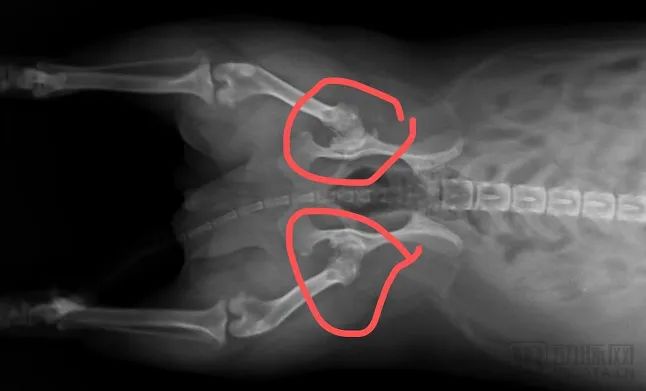

從那時(shí)開始,劉小姐開始頻繁地帶Tony前往附近的寵物醫(yī)院進(jìn)行檢查,陸陸續(xù)續(xù)給小狗做了全身X光、心臟超聲等影像學(xué)檢查,這才得知Tony的髖關(guān)節(jié)已經(jīng)嚴(yán)重磨損,心臟也比正常的大了20%。一個(gè)月折騰下來,影像檢查加上各類治療藥物總算讓Tony的生活恢復(fù)了正常,但前前后后花了劉小姐近3000塊錢。

Tony的髖關(guān)節(jié)X光影像